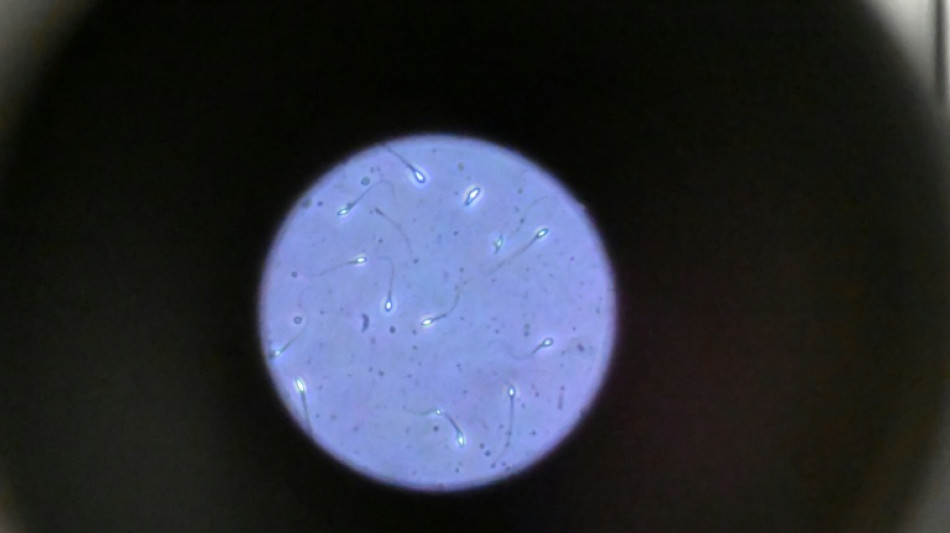

Dans l'espace, les spermatozoïdes ont du mal à trouver leur chemin / Photo: Damien MEYER - AFP/Archives

Dans l'espace, les spermatozoïdes ont du mal à trouver leur chemin vers l'ovule en raison de la microgravité, qui perturbe aussi le développement des embryons, selon une étude publiée jeudi dans Communications Biology.

Une des difficultés réside dans le fait que le sperme n'est plus attiré vers le bas par la gravité terrestre.

"Les spermatozoïdes doivent activement trouver leur chemin vers l'ovule et cette étude est la première à tester leur capacité à le faire dans des conditions semblables à ce qui se passe dans l'espace", explique à l'AFP Nicole McPherson, autrice principale de l'étude et chercheuse à l'Université d'Adelaïde (Australie).

Son équipe a utilisé une chambre en plastique imitant l'appareil génital féminin, qui leur a servi de "parcours d'obstacles miniature". "Voyez ça comme un minuscule circuit de course... Les spermatozoïdes étaient introduits à une extrémité et devaient nager jusqu'à l'autre bout", décrit-elle.

Les chercheurs ont testé successivement du sperme de souris et humain dans ce dispositif placé dans un appareil en constante rotation pour simuler la microgravité.

Les gamètes ont été environ 50 % moins performants pour naviguer à travers ce parcours que sous la gravité terrestre. Cela équivaut à une baisse de 30% du taux de fécondation réussie, selon les résultats de l'étude.